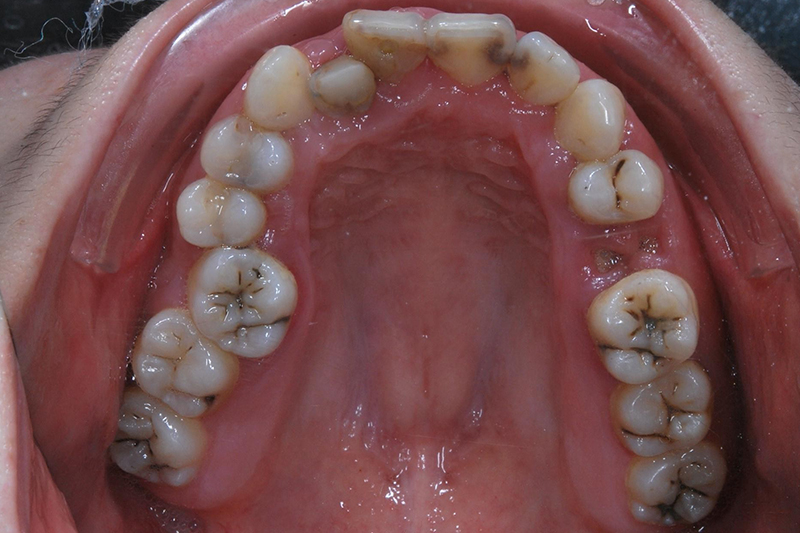

齒列不整

矯正前